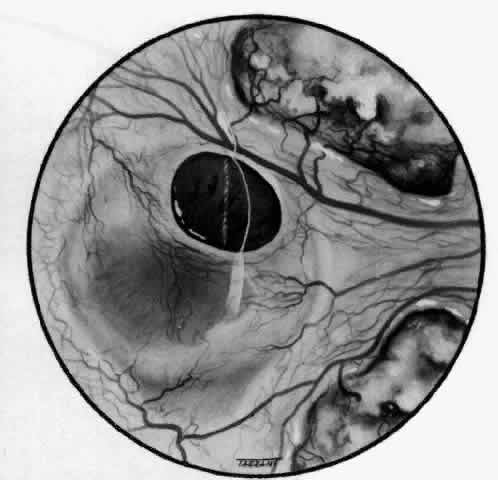

With the increasing use of anterior segment fluorescein angiography in the early detection of severe necrotizing disease of the sclera, it is necessary to have an understanding of the normal anatomy of the vasculature of the anterior segment of the eye.3–5 The blood supply to this region is enormous, being derived from the anterior ciliary arteries, but with extensive collateral arterial anastomoses to the posterior ciliary arteries at the root of the iris (Fig. 1). The anterior system is readily visible with the slit lamp and by anterior segment fluorescein angiography, especially if the eye is inflamed, and its recognition is of vital importance in the differentiation of episcleral and scleral conditions. The separation and displacement of these vascular layers give the most important clinical clues to the site and, hence, the severity of the inflammation. On slit lamp examination, three layers of vessels are readily visible. The conjunctival plexus, which is the most superficial layer of vessels, can be moved over the underlying structures. The superficial episcleral capillary plexus (Fig. 2) is a radially arranged series of vessels lying within the parietal layer of Tenon's capsule. The vessels in this layer anastomose at the limbus with the conjunctival vessels, with other members of the same plexus, and with the deep plexus. The deep episcleral capillary network (see Fig. 2) is closely applied to the sclera in the visceral layer of Tenon's capsule. The vessels anastomose freely with each other, forming a syncytium. The large vessels to and from the intrascleral plexus traverse the episclera near the insertions of the muscles. The conjunctival and superficial episcleral vessels can be blanched with 1:1000 epinephrine or 10% phenylephrine, but the deep vessels are affected slightly. This is of considerable assistance when attempting to differentiate deep and superficial inflammation.

Fig. 1. Anterior view montage of a cynomolgus monkey ocular casting with Tenon's and episcleral vessels removed. The anterior ciliary arteries (ACA) arborize at the limbus and interconnect via their lateral branches to form the episcleral circle. (CM, ciliary muscle capillary bed; CV, choroidal veins; EC, episcleral circle. (Original magnification, X20). (Morrison JC, van Buskirk EM: Anterior collateral circulation in the primate eye. Ophthalmology 90:707, 1983)